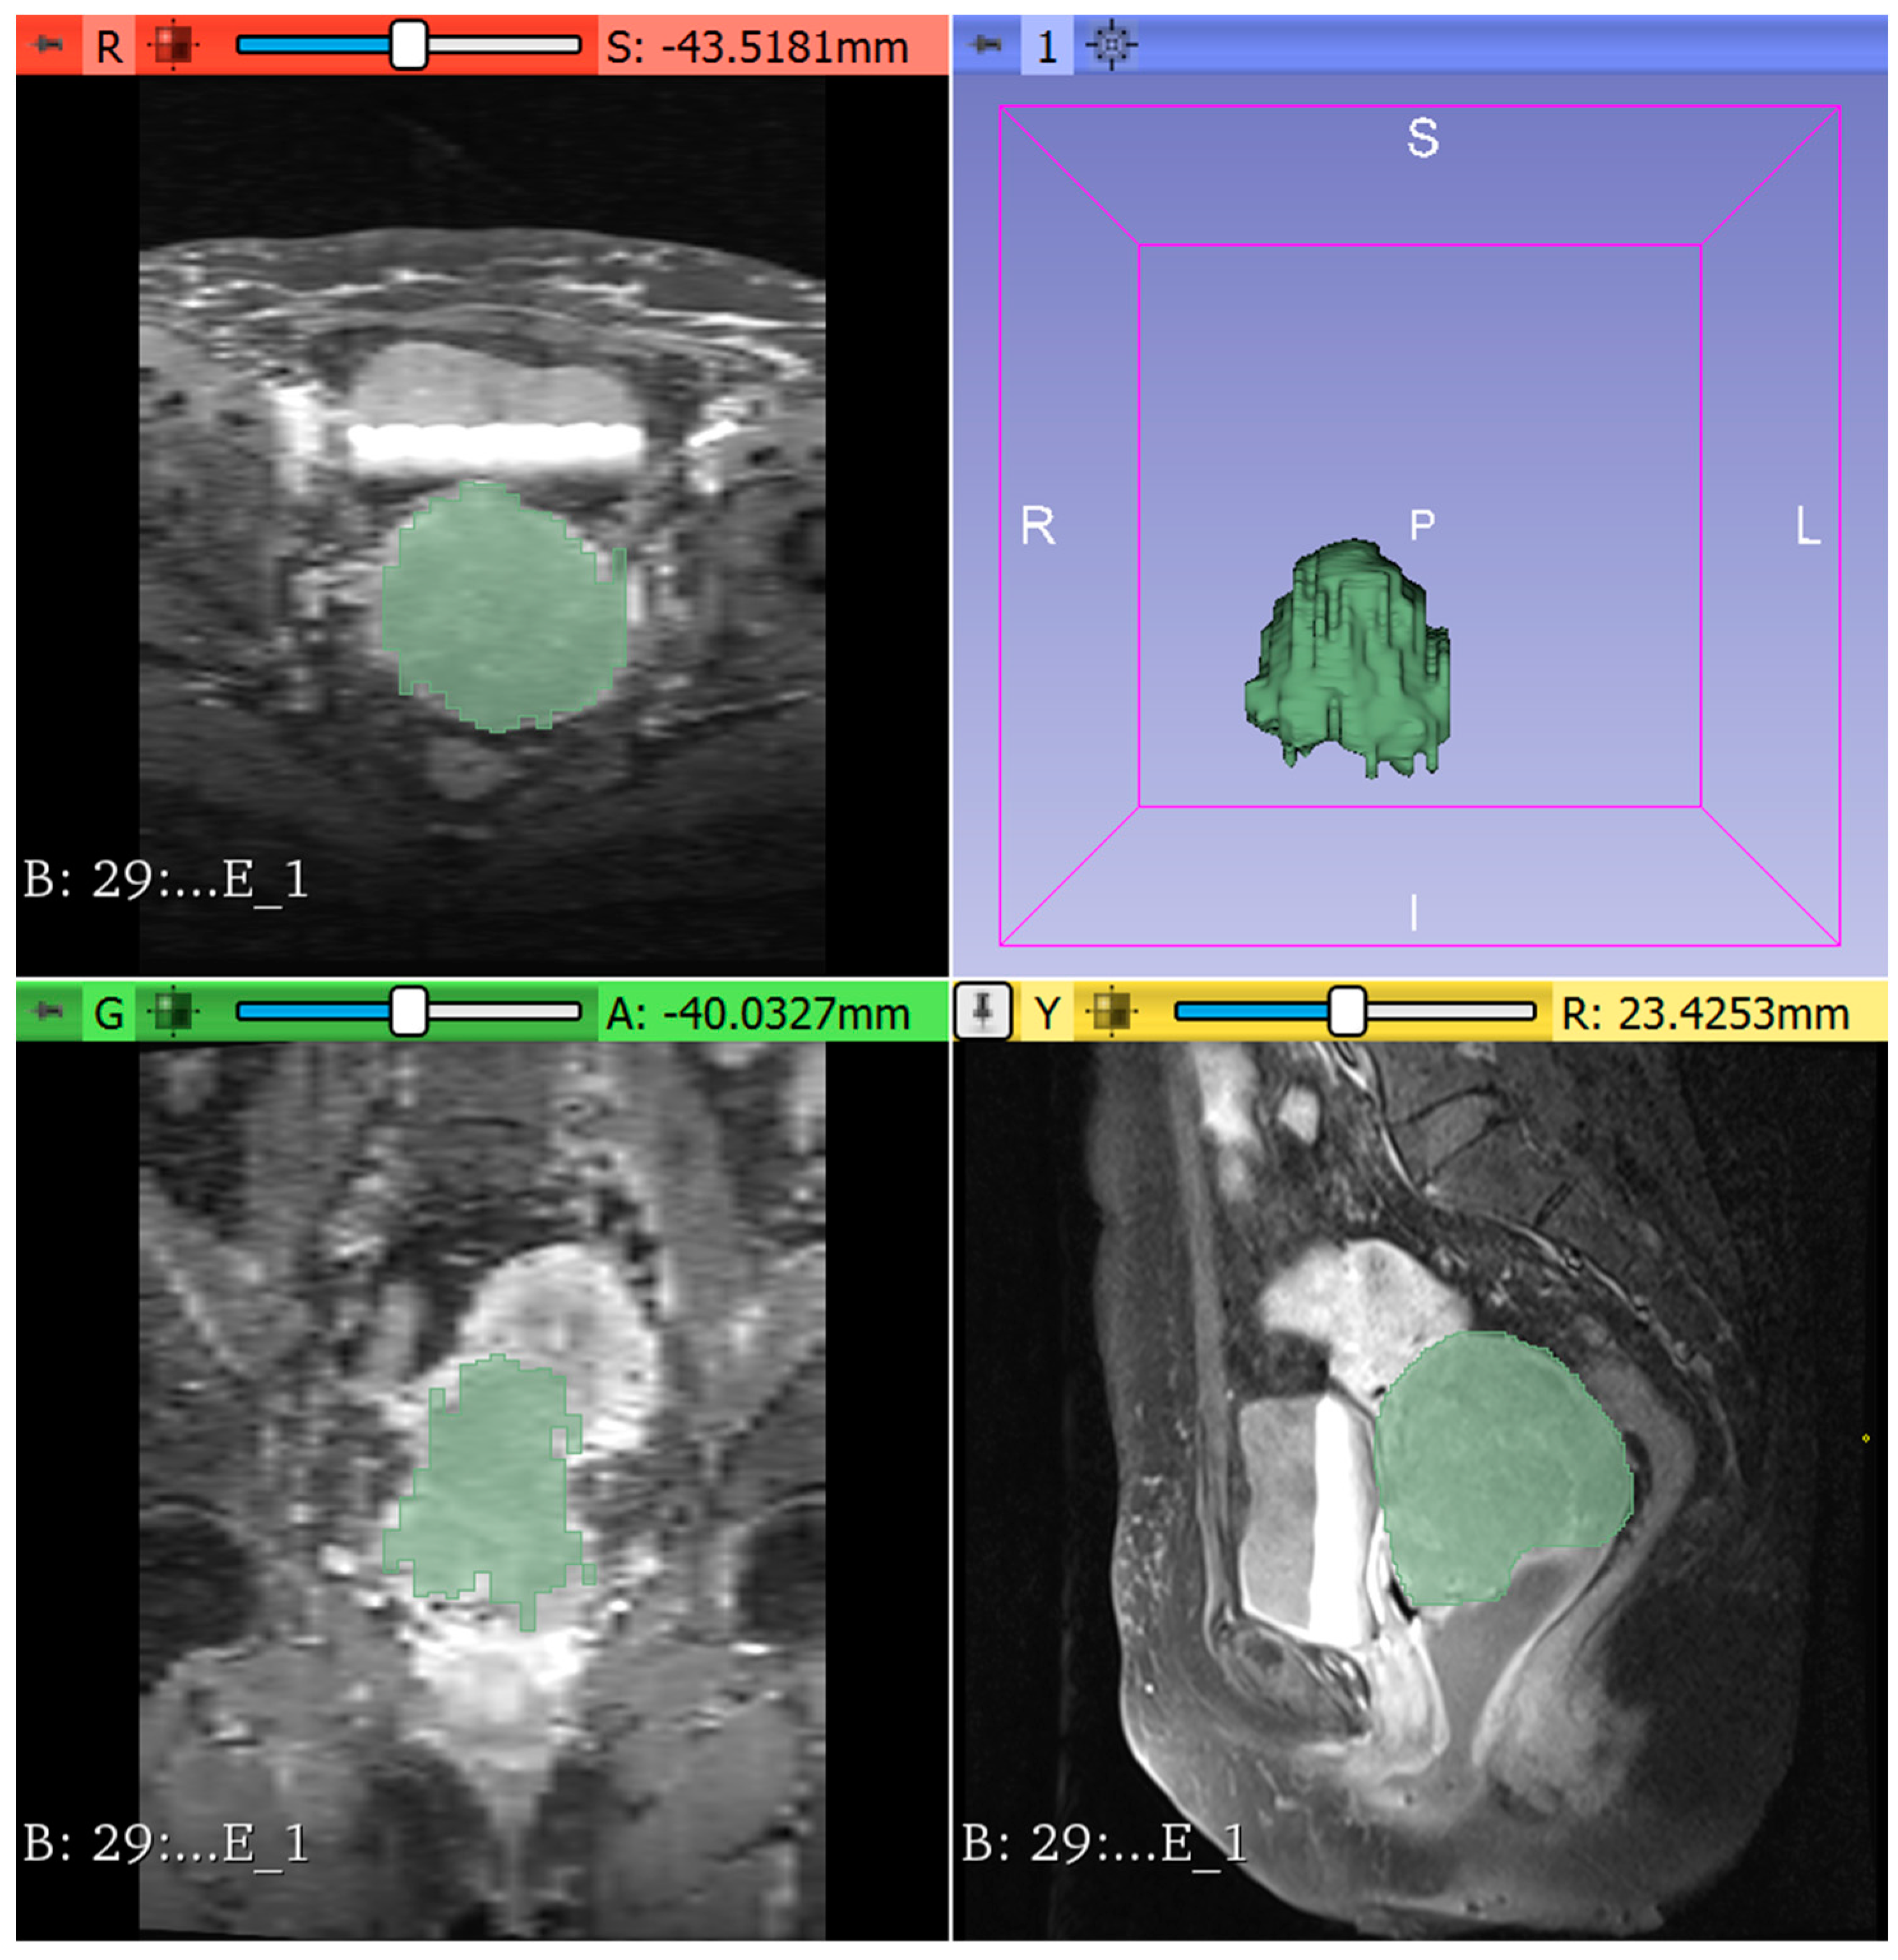

2.2. Semi-Automatic Segmentation